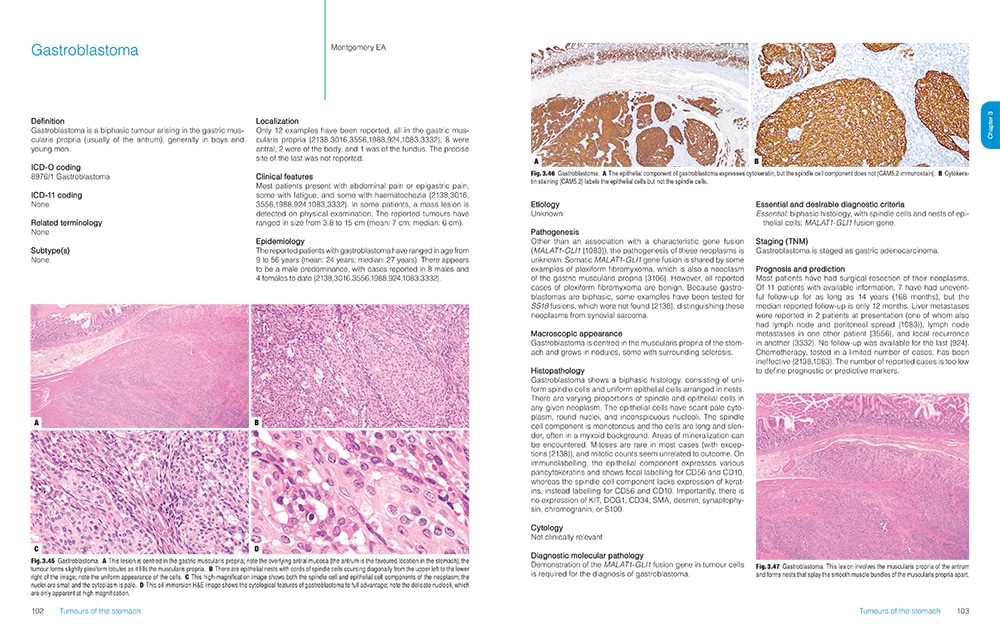

Featuring more than 1,000 high-resolution color graphics, Digestive System Tumours, the first volume of the fifth edition of the WHO series known as the Blue Books, brings a noticeable improvement in image quality and graphic design over the fourth edition, published in 2008. The book’s two-column layout, replacing the former three-column design, allows for enlarged images throughout. And this book is the first to be produced in both a print version and an online subscription version that includes whole-slide imaging.

The fourth edition of the WHO series set a whole new standard and raised the bar considerably from the third edition, Dr. Cree says. “And we are honestly trying to do the same with the fifth edition.” The new online subscription feature, for example, is intended not only to make user access easier but also to show significantly more content. “We have a whole-slide image for each diagnosis in the book. Whole-slide images allow us to get an overview of the entire section of the slide right down to the individual cells and see what is going on.” In addition, each paper in the book has a direct online link to the evidence that underpins the paper, he notes.

Pathologists learn so much from their exposure to illustrations, he says, and high-quality graphics have always been a feature of the WHO Blue Books. “When you collect world experts together and they all have their archives of gross photographs and microscopic slides, you can produce the best examples and most classic illustrations of the features.”

Now, the incorporation of digital slides will allow an interactive experience for the reader, who will be able to look at not just a single snapshot, such as would appear in a book, but also different magnifications that can be examined more comprehensively. This capability has become practical only in the past few years, Dr. Klimstra says. The WHO has learned from the experience of PathPresenter, which has created an educational portal for digital slides that is now an entirely new feature of the WHO series.